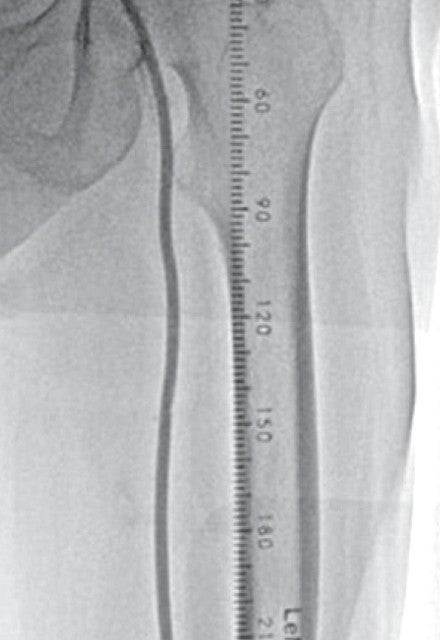

右大腿動脈穿刺、0.035 inchワイヤーを用いて、ガイディングシース 6 Fr 60 cmを左外腸骨動脈まで誘導し、造影を行った(図1.2)。体表面エコーガイドのもと、マイクロカテーテルと0.014 inch フロッピー300 cmワイヤーで、確実に浅大腿動脈入口部から血管真腔内を進めた。0.014 inch フロッピー300 cmワイヤーを抜去し、血管狭窄部貫通用カテーテルに交換し、閉塞部位を慎重に進め、貫通に成功した。血管狭窄部貫通用カテーテルにエクステンションワイヤーをつなげ、マイクロカテーテルを抜去、0.018 inchの径 2.0/長 20 mmバルーンで閉塞部位を拡張した。マイクロカテーテルを末梢まで進め、血管狭窄部貫通用カテーテルを抜去、0.014 inch 300 cm ワイヤーに交換、血管内超音波で病変部の観察を行った。ほぼ真腔を捉えていることが確認できたため、径 4.0/長 250 mmバルーンで閉塞全域を拡張した。一部石灰化病変により、拡張不良部位を認めたため(図3)、径 3.0/長 40 mm ノンコンプライアントバルーンで追加拡張を行った。再度、径 4.0/長 250 mmバルーンで閉塞全域を拡張した(図4)。血管内超音波で閉塞領域を観察し、ほぼ真腔を捉えていることが確認できた。ついで、径 5.0/長 250 mmバイアバーン® ステントグラフトを留置し、グラフト内をバルーンで後拡張した。血管内超音波でグラフト拡張および浅大腿動脈入口部を確認した(図5.6)。結果、左浅大腿動脈の良好な血流を得た(図7)。

体表面エコーでのフォローアップ : 1か月後、3か月後、6か月後、9か月後、1年後、1.5年後にチェックし、すべて開存確認し得た。

血圧脈波(ABI):治療前 0.78、1か月後 0.98、1.5年後 0.92と大きな変化なく、安定している。